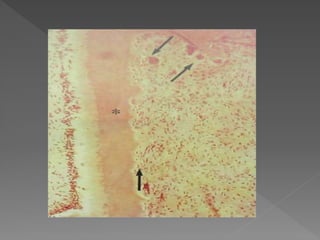

• #64 In the early stages, the résorption cavity contains a mass of fibrous tissue, numerous blood vessels and clastic resorbing cells adjacent to the dentin surface [Fig 13). Clastic cells lining the resorptive cavities are generally mononuclear, but some multinucleated cells can also be identified. A layer of dentin and predentin separates the resorbing tissue from the dental pulp, which remains free of inflammation until late in the process. The resorbing tissue is usually devoid of acute or chronic inflammatory cells unless the lesion has been invaded by oral microorganisms. These early lesions contain fibrovascular tissue, but they appear to progress to fibro-osseous lesions by the deposition of ectopic bonelike calcifications both within the resorbing tissue and directly onto the resorbed dentin surface.

• #65 The odontoclast in the lacuna exhibits a developed ruffled border (small arrows), a clear zone (CZ), abundant vacuoles (V) and mitochondria (small arrowheads), and scattered rER (open arrowheads), which indicate that this odontoclast is activated for root resorption. Mononuclear cells (arrows) close to the odontoclast-detached surface are extending cytoplasmic processes (arrowheads) toward the root surface.

• #66 Resorption channels are created; these burrow deeply into the dentin surrounding the root canal and later interconnect more apically with the periodontal ligamentAs a result, a delta of channels may be created, which has the effect of increasing the

• #67 potential for further résorption. The ectopic bonelike tissue that is deposited within the fibrovaseuiar tissue and directly onto dentin has a eanalicular structure with cellular inclusions and resembles cancellous bone. As lesions become more extensive and there is cavitation into the oral cavity, secondary invasion of the tissue by microorganisms attracts a normal inflammatory response cbaracterized by tbe presence of acute and cbronic inflammatory cells. Despite this, the pulp will often remain free of inflammation (Fig 15) unless tbere is penetration into the pulp space by tissue accompanied by microorganisms. In some instanceswhen the pulp space is invaded by resorbirtg tissue

• #70 a place in which something is formed or deposited; a site of origin- nidus